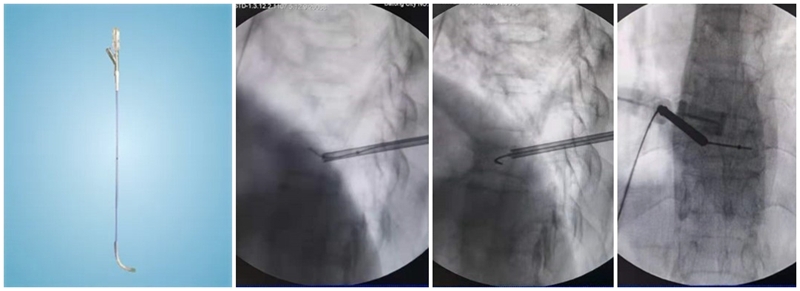

(1)定位与穿刺:透视下确定伤椎椎弓根外缘上1/3 入路点及伤椎上终板或下终板方向并做好标记。由于穿刺容错率高,穿刺针(4. 2 mm)不用过度内倾,不必苛求针尖在椎体内侧壁、后壁位置,穿刺针从椎弓根外缘沿椎弓根方向缓慢穿刺入椎体即可,针尖务必穿刺入椎体后1/3。

(2)弯角导丝开腔:弯角骨钻开腔器械刺入椎体时,注意开腔工具手柄与伤椎终板平行,不要强行开腔,多透视侧位,否则弯导丝可能穿破终板,导致医源性骨水泥渗漏。C形臂X线机正位透视下,导丝到达椎体对侧椎弓根处即可。

(3)弯角骨钻扩张:C形臂X线机正位透视下,弯角骨钻开腔器械螺旋手柄顺时针扭转,让弯角骨钻沿导丝前进开路,将椎体内部钻出弧形通道。操作中注意骨钻沿导丝旋进旋出要完全,旋进不够,后期球囊无法到达对侧,旋出不完全,骨钻会卡在工作套筒上无法拔出。

(4)置入球囊:插入带导丝弯角球囊时注意透视球囊方向,反复调整务必与终板平行。如需要拔出球囊调整方向,务必先拔导丝再拔球囊,透视球囊标记点必须完全从工作套管内出来,否则易造成弯角球囊与工作套管边缘卡磨破裂。

(5)扩张球囊:注入造影剂扩张球囊过程中,注意观察术中正侧位透视图像,控制压力值,不必苛求球囊顶到上下终板,以免发生医源性终板破裂,造成椎间隙骨水泥渗漏可能。注意弯角球囊扩张完毕后拔除顺序:先拔导丝再拔球囊。